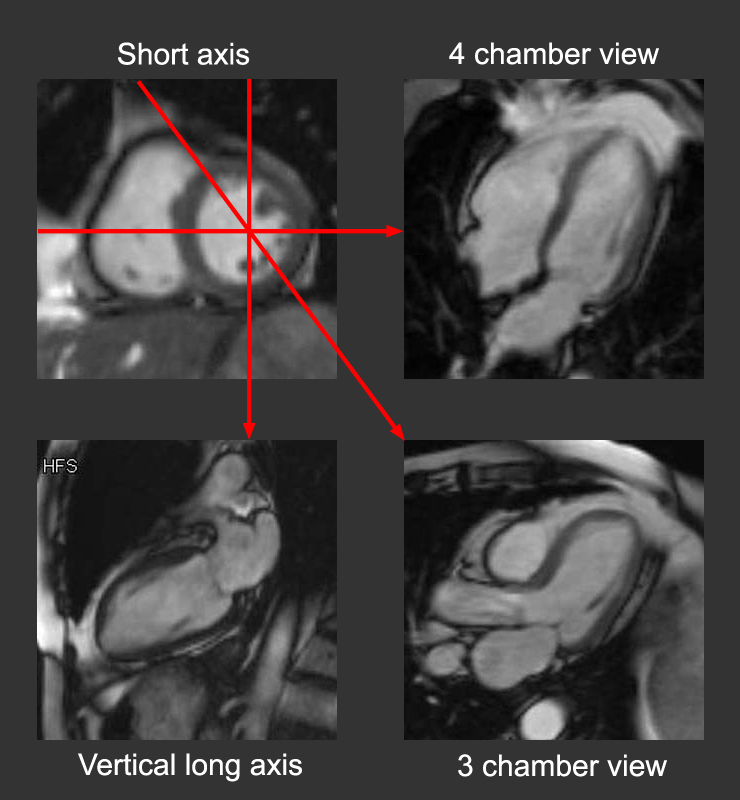

Cardiac MRI > Anatomy > Relationship of Basic Views

Relationship of Basic Views